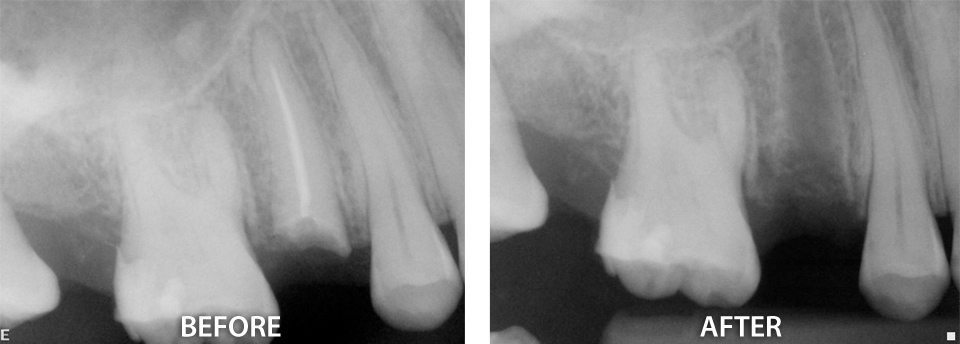

Our office offers a variety of surgical procedures designed to improve oral health and eliminate pain. We help with extractions of impacted wisdom teeth and retained “baby” teeth that are in the way of erupting permanent teeth. Other treatments include removal of excess or swollen gums around erupted or partially erupted teeth and elimination of problem tissue causing periodontal problems. In those cases where the complexity dictates, we have teamed up with surgery specialists that help us make procedures smooth and easy. Click here to find out more.